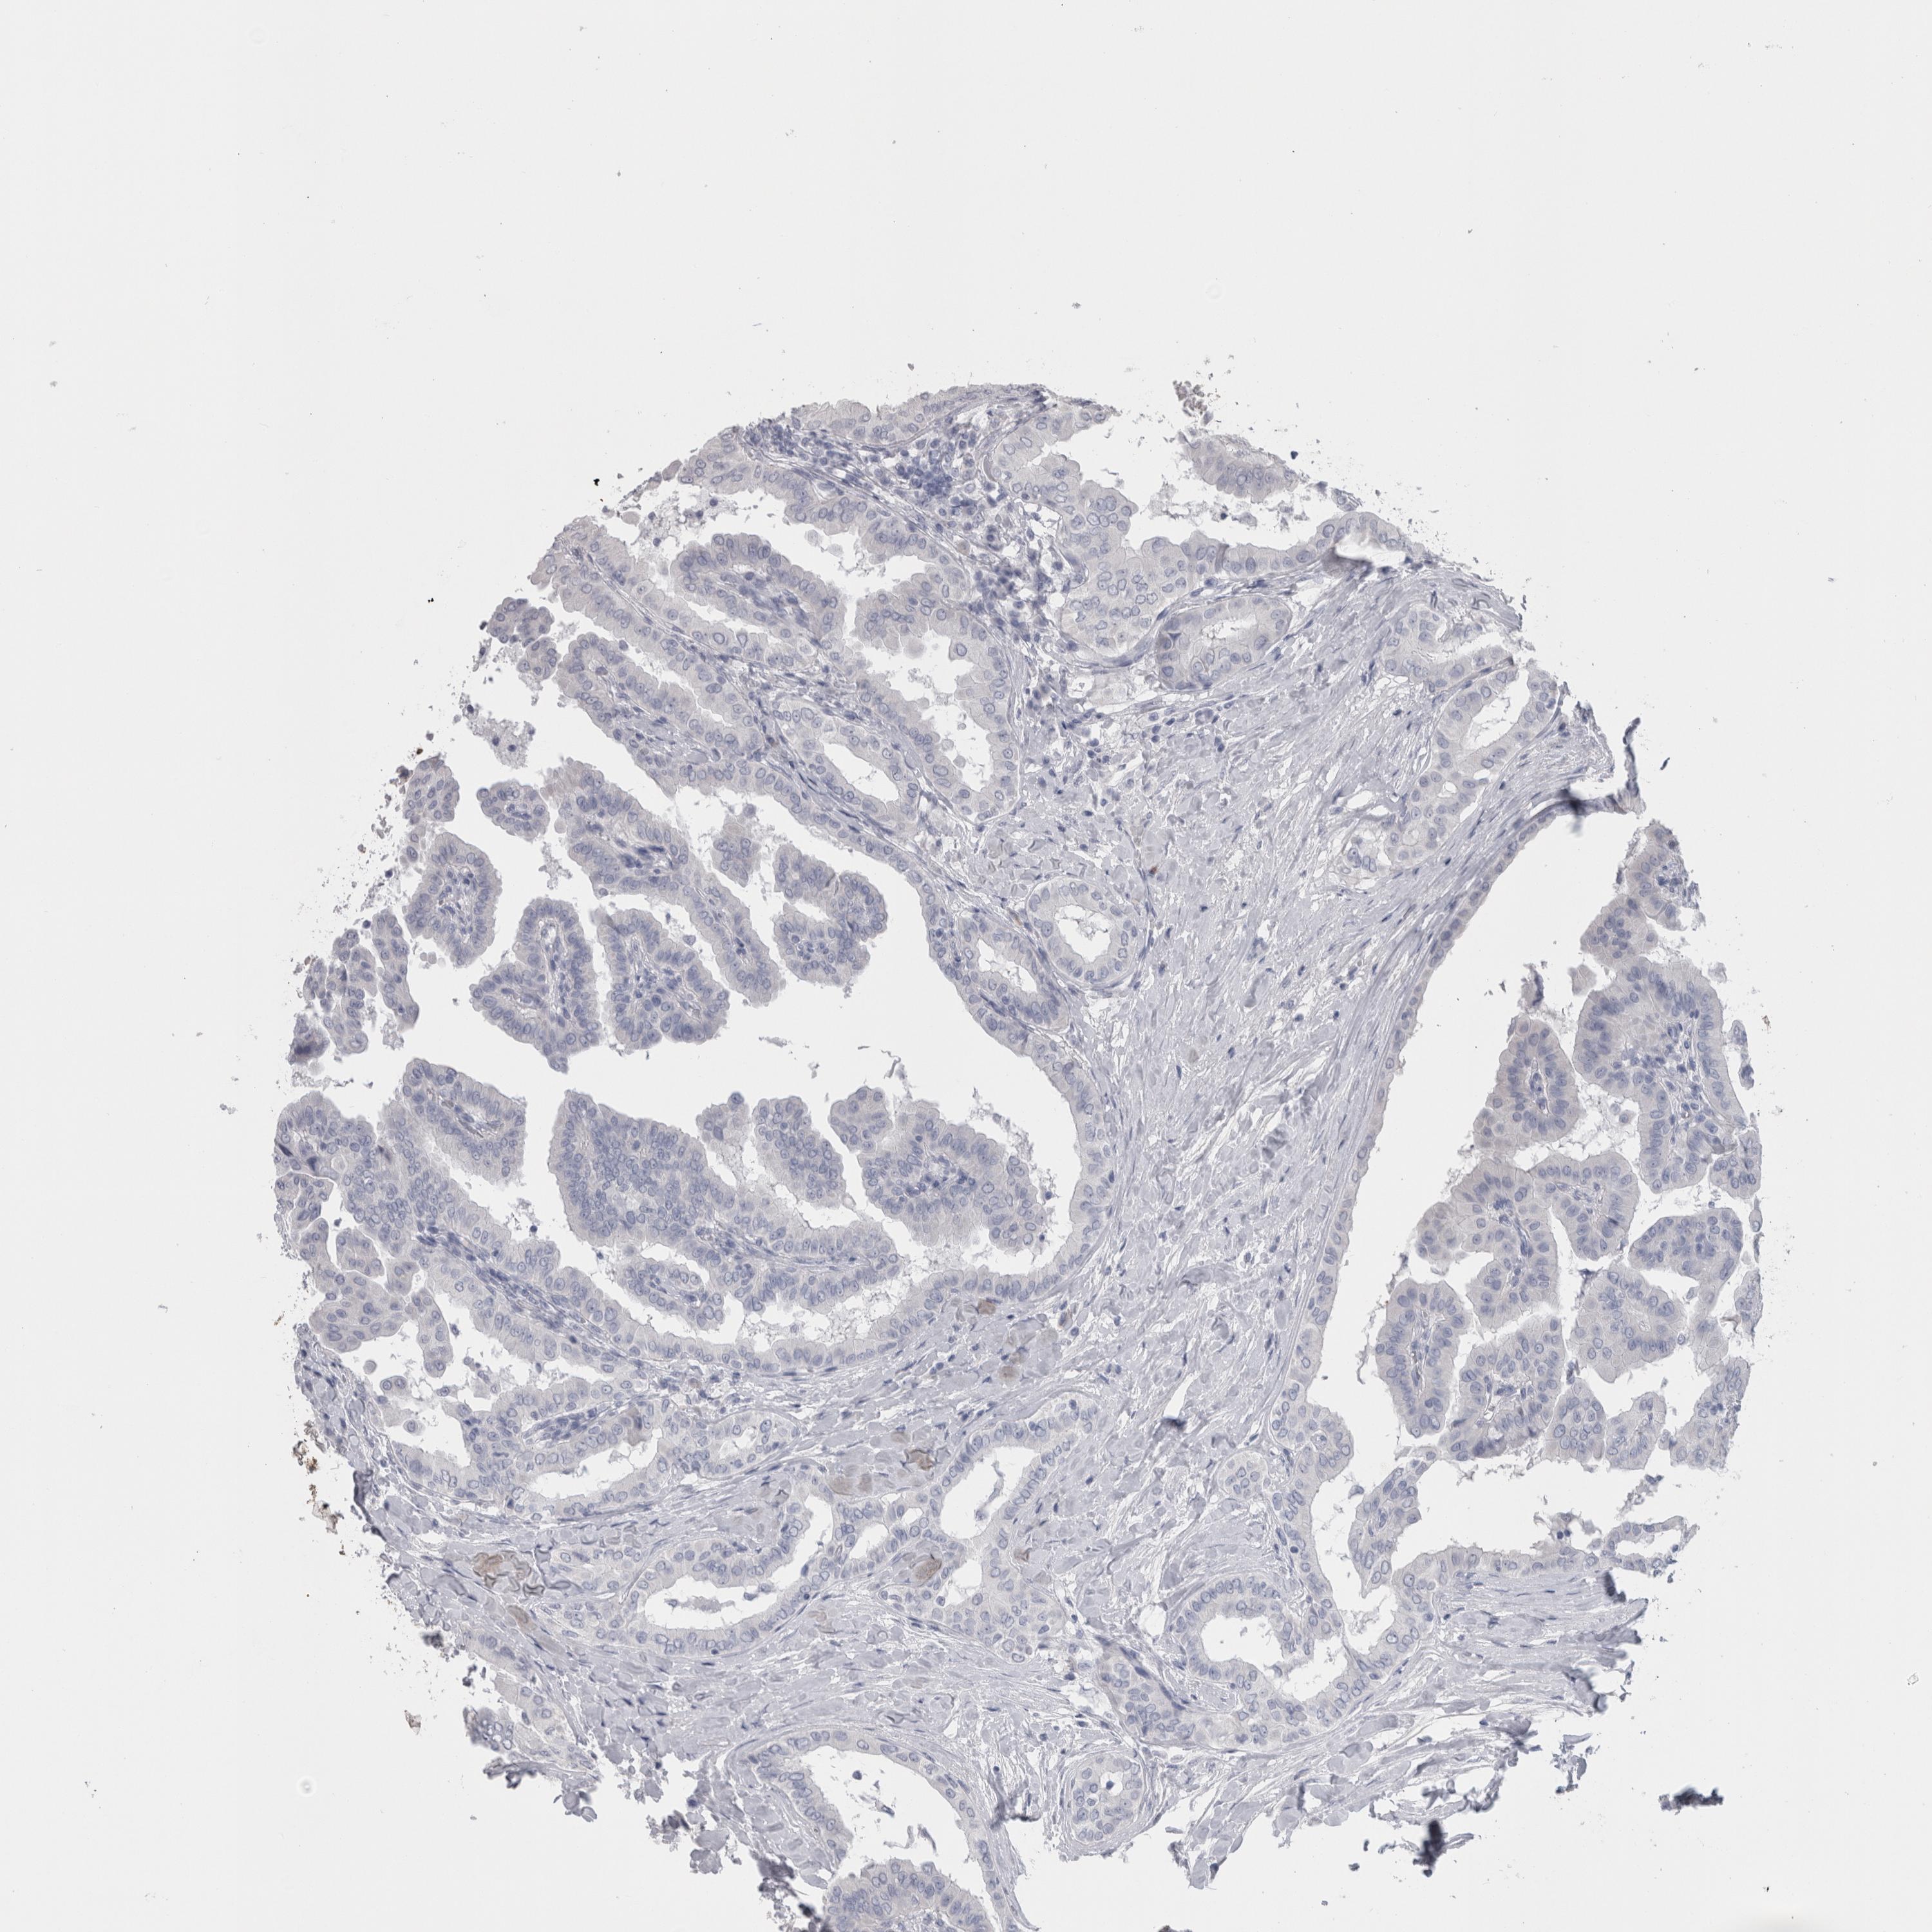

THYROID CANCER - Protein expressioni

A mouse-over function shows sample information and annotation data. Click on an image to view it in a full screen mode. Samples can be filtered based on level of antibody staining by selecting one or several of the following categories: high, medium, low and not detected. The assay and annotation is described here.

Note that samples used for immunohistochemistry by the Human Protein Atlas do not correspond to samples in the TCGA dataset.

Antibody stainingi

Antibody staining in the annotated cell types in the current human tissue is reported as not detected, low, medium, or high, based on conventional immunohistochemistry profiling in selected tissues. This score is based on the combination of the staining intensity and fraction of stained cells.

Each image is clickable and will lead to virtual microscopy that enables deeper exploration of all samples and also displays staining intensity scores, fraction scores and subcellular localization as well as patient and tissue information for each sample.

Antibody HPA051257

Antibody CAB026357

Staining

High

Medium

Low

Not detected

Intensity

Strong

Moderate

Weak

Negative

Quantity

>75%

75%-25%

<25%

None

Location

Nuclear

Cytoplasmic/membranous

Cytoplasmic/membranous,nuclear

Papillary adenocarcinoma, NOS

Follicular adenoma carcinoma, NOS